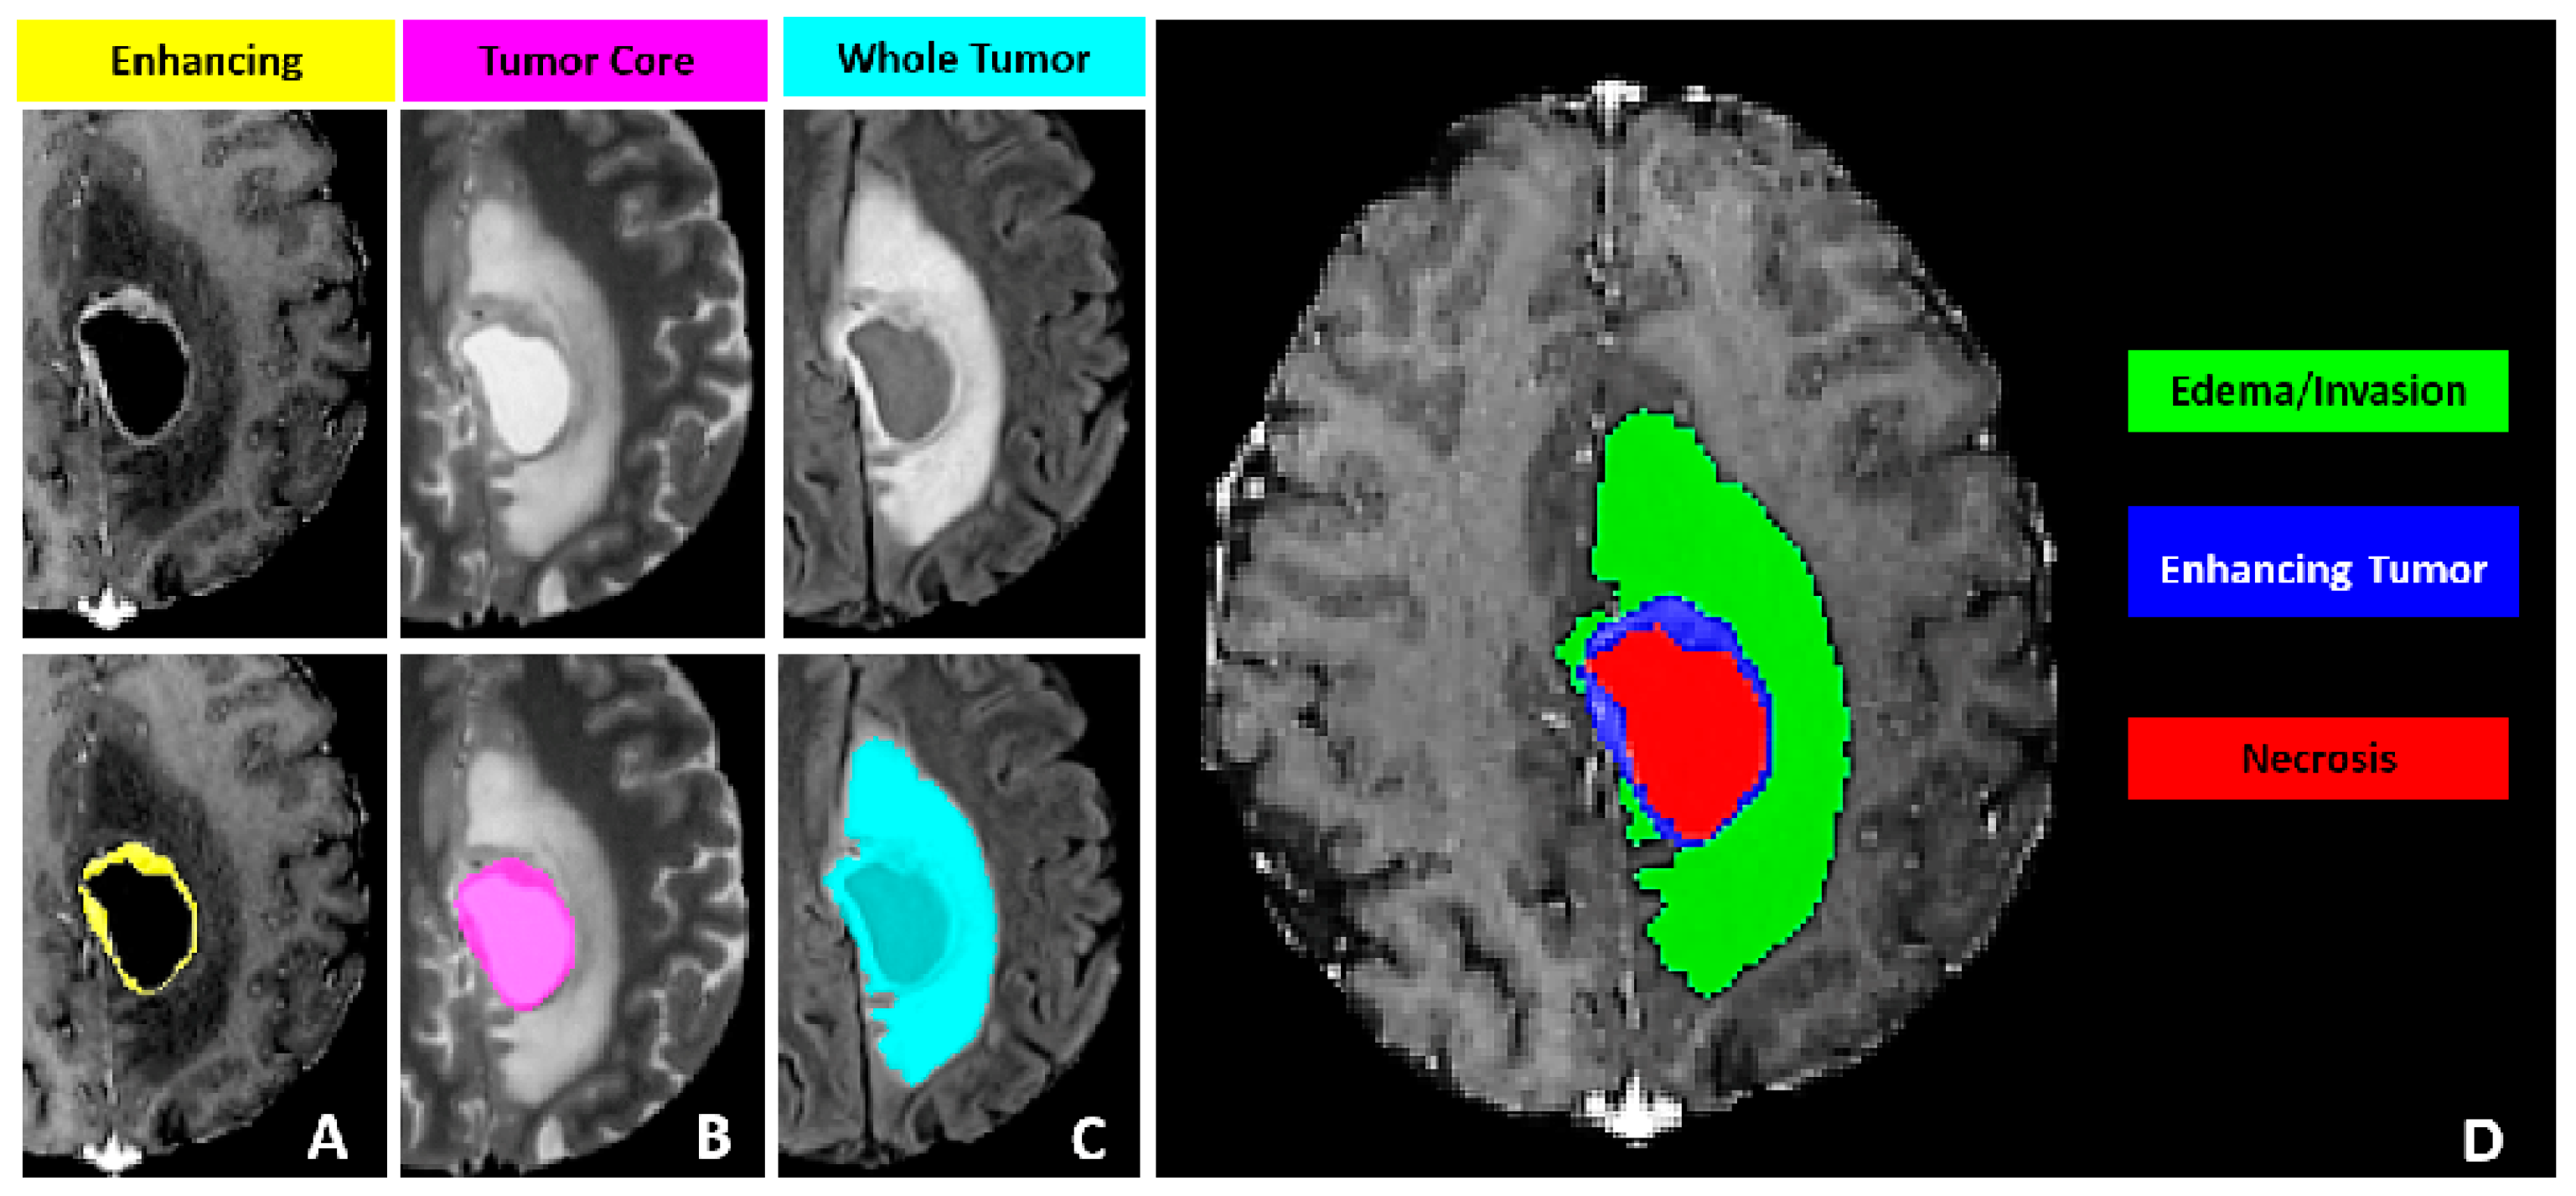

Previous medical image segmentation studies have encountered challenges in discerning different adjacent pathological areas. For instance, within the dataset employed in our investigation, distinguishing between the enhanced tumor (ET) and the edema/necrotic tissue (ED), as well as differentiating the necrotic tumor core (NCR) from the surrounding tissue, has been notably difficult.

Furthermore, the precise definition of the tumor lesion’s periphery continues to present a significant challenge in the field of medical image analysis in Figure 2. An enhanced attention mechanism is introduced which emphasizes the features of the edge regions. The attention module is operationalized through the following equation,

The tumor sub-regions annotated are based on observable features recognizable by trained radiologists (referred to as VASARI features) and include the following. The Gd-enhancing tumor (ET) labeled as 4, which represents the enhancing part of the tumor visible on T1Gd MRI scans, including areas of strong and faint enhancement. The peritumoral edematous/invaded tissue (ED) labeled as 2, which is characterized by an abnormal hyperintense signal on T2-FLAIR volumes, encompassing the infiltrative non-enhancing tumor and vasogenic edema in the peritumoral region. The necrotic tumor core (NCR) labeled as 1, which appears hypointense on T1Gd MRI and represents the non-viable, necrotic center of the tumor. This is illustrated in Figure 5.

Figure 5. Glioma sub-regions considered in the MICCAI BRATS 2021 challenge. (A) displays the enhancing (yellow) and tumor core (pink) areas; (B) shows the whole tumor (light blue) area; (C) presents the edema/invasion (green) and enhancing tumor (blue) areas; (D) depicts the necrosis (red), enhancing tumor (blue), and edema/invasion (green) areas, comprehensively representing the different sub - regions of the tumor.